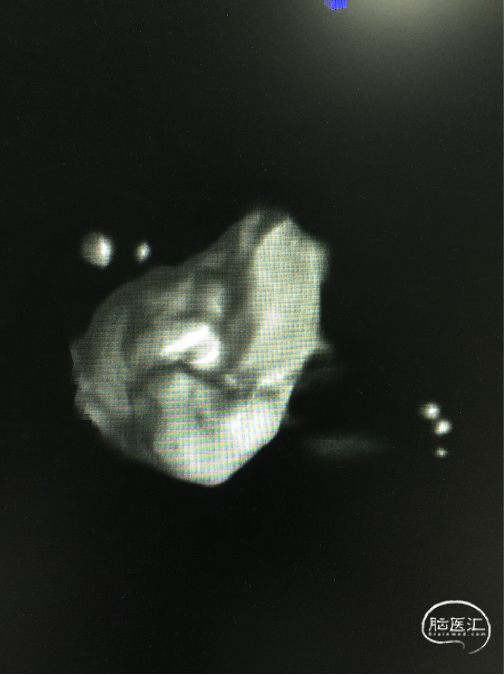

SL-10(直头)置于RACA A2,Atlas支架(直径3.0mm,较血管直径2.0mm大一号)到位,头端在RACA A2(左图);SL-10(头端S型)置于AcoAn左侧分叶(右图)。

支架释放

Atlas支架原位释放,头端打开良好,中部因较血管管腔大,可实现穹隆效果,以保护LACA A2流入道,尾端即将完全释放(左图);Atlas支架继续完全释放,尾端打开良好(右图)。

穿网孔超选

将直头SL-10穿过Atlas网眼超选入动脉瘤右侧分叶(左图),蒙片显示Altas形态及双微导管头位置,到达理想位置(右图)。